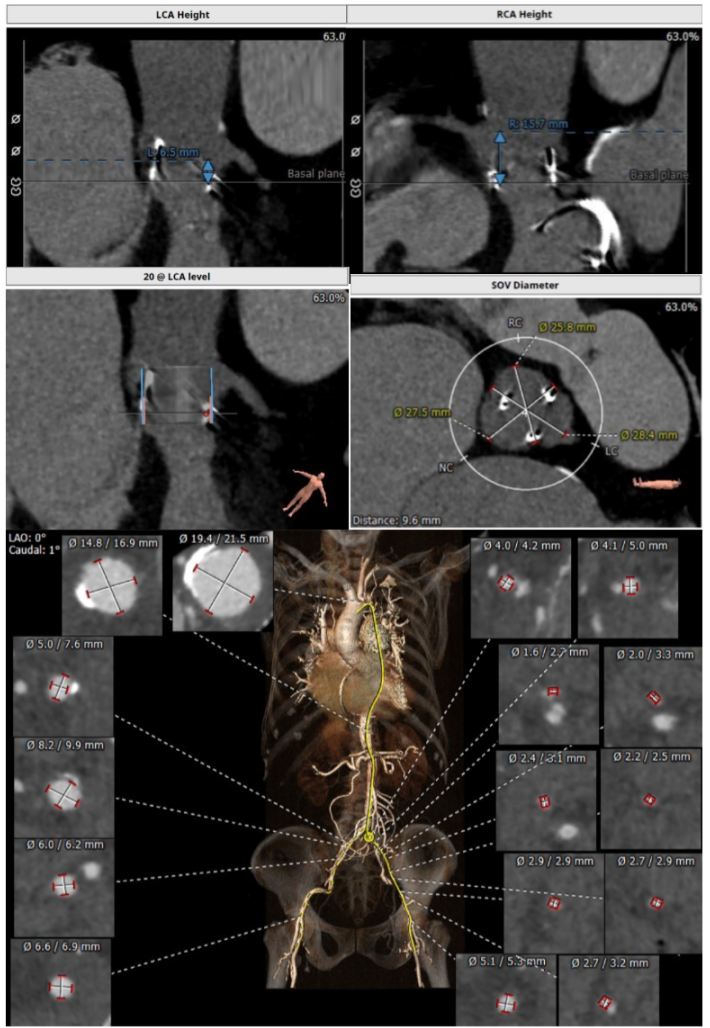

经过充分的术前食道超声及心脏CTA的评估,团队一致选择目前国际上瓣中瓣(Valve in Valve)技术使用最多最成熟的器械——Edwards SAPIEN3瓣膜。与林阿姨及其家属充分沟通后,在经验丰富的王焱院长的指导下,珠海市人民医院结构性心脏病团队决定为林阿姨同期进行主动脉瓣及二尖瓣的双瓣膜置换,采用的方案是先经股动脉途径为其行主动脉瓣的瓣中瓣植入(VinV TAVR),然后经股静脉途径,穿刺房间隔后,行二尖瓣的瓣中瓣植入(VinV TMVR),视情况对房间隔穿刺后的缺损进行封堵。

主瓣瓣中瓣CT评估